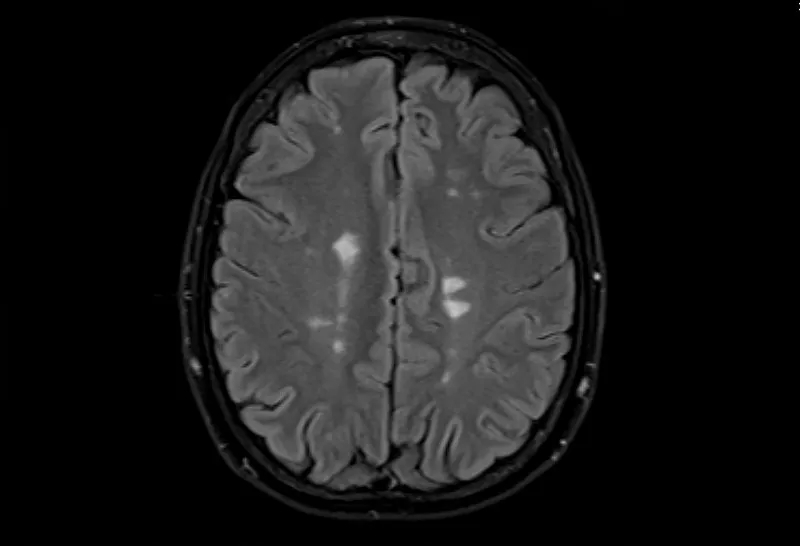

• 大腦的MRI掃描可以顯示損傷區域,但沒(méi)有單一的測試可以診斷MS。

多發(fā)性腦硬化癥的磁共振成像,軸位Flair視圖

測試的組合用于診斷MS。最好的測試是對您的大腦和脊髓進(jìn)行核磁共振檢查,以檢測損傷區域。您可能還需要進(jìn)行血液檢查、腰椎穿刺和測量神經(jīng)活動(dòng)的測試。